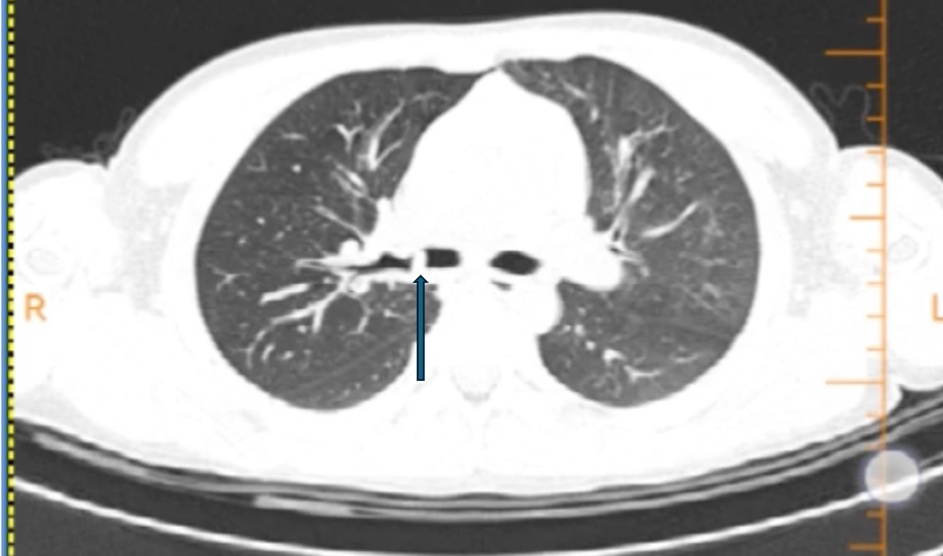

箭头为右主支气管高密度影

CT检查结果显示,乐乐右主支气管有可疑阴影

右侧肺还有个肺大泡